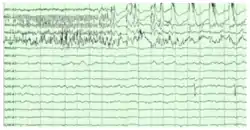

The hippocampus shows two major "modes" of activity, each associated with a distinct pattern of neural population activity and waves of electrical activity as measured by an electroencephalogram (EEG). These modes are named after the EEG patterns associated with them: theta and large irregular activity (LIA). The main characteristics described below are for the rat, which is the animal most extensively studied.[67]

The theta mode appears during states of active, alert behavior (especially locomotion), and also during REM (dreaming) sleep.[68] In the theta mode, the EEG is dominated by large regular waves with a frequency range of 6 to 9 Hz, and the main groups of hippocampal neurons (pyramidal cells and granule cells) show sparse population activity, which means that in any short time interval, the great majority of cells are silent, while the small remaining fraction fire at relatively high rates, up to 50 spikes in one second for the most active of them. An active cell typically stays active for half a second to a few seconds. As the rat behaves, the active cells fall silent and new cells become active, but the overall percentage of active cells remains more or less constant. In many situations, cell activity is determined largely by the spatial location of the animal, but other behavioral variables also clearly influence it.

The LIA mode appears during slow-wave (non-dreaming) sleep, and also during states of waking immobility such as resting or eating.[68] In the LIA mode, the EEG is dominated by sharp waves that are randomly timed large deflections of the EEG signal lasting for 25–50 milliseconds. Sharp waves are frequently generated in sets, with sets containing up to 5 or more individual sharp waves and lasting up to 500 ms. The spiking activity of neurons within the hippocampus is highly correlated with sharp wave activity. Most neurons decrease their firing rate between sharp waves; however, during a sharp wave, there is a dramatic increase of firing rate in up to 10% of the hippocampal population

Theta rhythm

Because of its densely packed neural layers, the hippocampus generates some of the largest EEG signals as theta waves of any brain structure, which generate the hippocampal theta rhythm.[70] In some situations the EEG is dominated by regular waves at 3 to 10 Hz, often continuing for many seconds. These reflect subthreshold membrane potentials and strongly modulate the spiking of hippocampal neurons and synchronise across the hippocampus in a travelling wave pattern.[71] The trisynaptic circuit is a relay of neurotransmission in the hippocampus that interacts with many brain regions. From rodent studies it has been proposed that the trisynaptic circuit generates the hippocampal theta rhythm.[72]

Theta rhythmicity is very obvious in rabbits and rodents and also clearly present in cats and dogs. Whether theta can be seen in primates is not yet clear.[73] In rats (the animals that have been the most extensively studied), theta is seen mainly in two conditions: first, when an animal is walking or in some other way actively interacting with its surroundings; second, during REM sleep.[74] The function of theta has not yet been convincingly explained although numerous theories have been proposed.[67] The most popular hypothesis has been to relate it to learning and memory. An example would be the phase with which theta rhythms, at the time of stimulation of a neuron, shape the effect of that stimulation upon its synapses. What is meant here is that theta rhythms may affect those aspects of learning and memory that are dependent upon synaptic plasticity.[75] It is well established that lesions of the medial septum—the central node of the theta system—cause severe disruptions of memory. However, the medial septum is more than just the controller of theta; it is also the main source of cholinergic projections to the hippocampus.[15] It has not been established that septal lesions exert their effects specifically by eliminating the theta rhythm.[76]